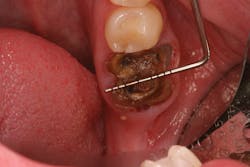

Because of this alveolar resorptive pattern after tooth extraction, bone grafting the extraction socket after tooth extraction procedures has become a solution that attempts to limit the amount of hard- and soft-tissue loss. There are many systematic reviews in the literature that compare the results of residual ridge dimension following tooth extraction after the use of a bone graft (with or without a membrane) versus extraction alone without grafting.7

• preserving tissue structure for subsequent dental implant therapy.Decision matrix